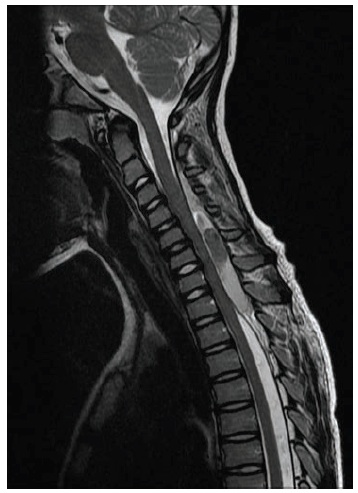

Thomas Nichols, MD; Neenah Sumon Bhattacharjee, MD; Scott Harbick, MD

<p><img src="/sites/default/files/transfer/MRI.jpg" width="115" height="115" style="float: left; margin-top: 5px; margin-bottom: 5px;">An 8-year-old boy...